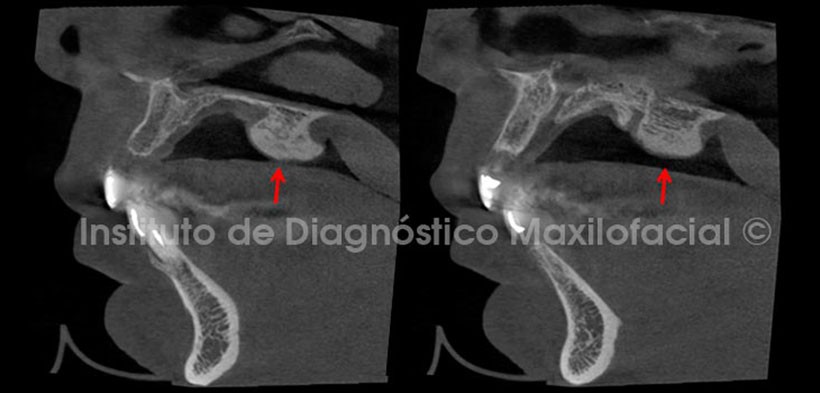

Mediante las vistas sagitales se observa a la entidad con una estrecha base y un aumento de sus dimensiones conforme se aleja de la superficie del paladar (Fig. 3).